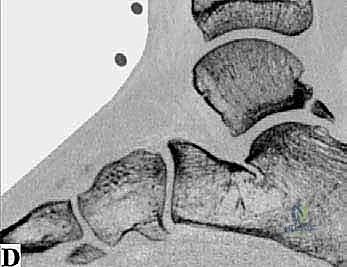

* الأشعة السينية (X-rays): بوضعيات خاصة (Lateral view) لرؤية العظم الزائد (Os Trigonum) والنتوءات العظمية وتضيق المسافات المفصلية.

* التصوير بالرنين المغناطيسي (MRI): هو المعيار الذهبي. يكشف بدقة متناهية عن التهابات الأوتار (مثل FHL)، ارتشاح السوائل، تمزقات الأربطة، ووذمة نخاع العظم (Bone Marrow Edema) التي لا تظهر في الأشعة العادية.

* الأشعة المقطعية (CT Scan): تُستخدم في حالات معينة لعمل خريطة ثلاثية الأبعاد للكسور القديمة أو التكلسات العظمية المعقدة قبل الجراحة.

1. متلازمة انحشار الكاحل الخلفي والعظم الزائد (Os Trigonum Syndrome)

تُعد هذه المتلازمة من أكثر الأسباب شيوعاً، خاصة لدى الرياضيين (لاعبي كرة القدم) والراقصين (الباليه). العظم الزائد (Os Trigonum) هو عظم إضافي خلقي صغير يقع خلف عظم الكاحل (Talus). في الحالات الطبيعية، قد لا يسبب ألماً، ولكن مع الثني القسري المتكرر للقدم نحو الأسفل (Plantar Flexion)، ينحشر هذا العظم بين عظم الظنبوب وعظم العقب، مما يؤدي إلى التهاب شديد وتمزق في الأنسجة المحيطة به.